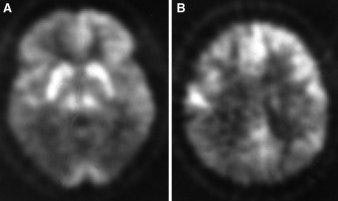

FDG-PET scans of 60-year-old man with a Creutzfeldt-Jakob disease. Note marked reduction in FDG uptake in temporo-parietal image at left, and parietal region, right (JNM, November 2000, Vol.41:11, p.1924).